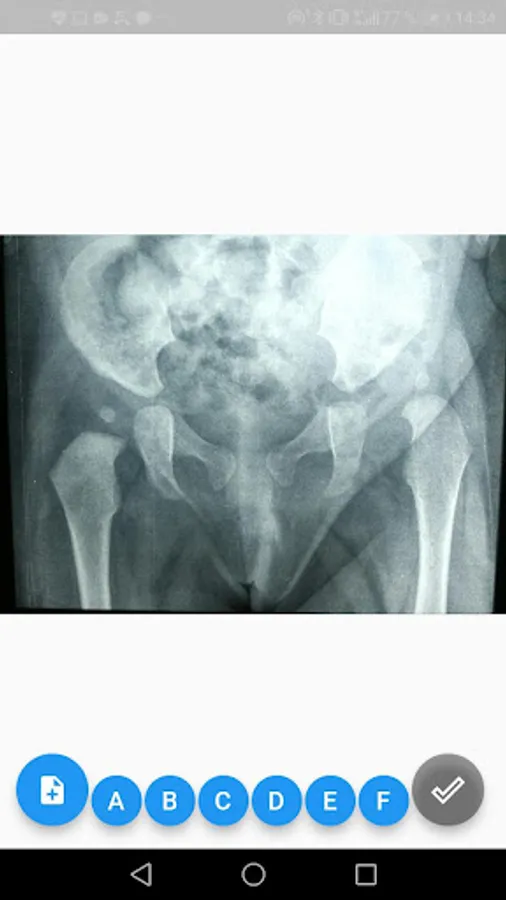

4. Add the picture taken by pressing the "+" icon (with the phone in an upright position).